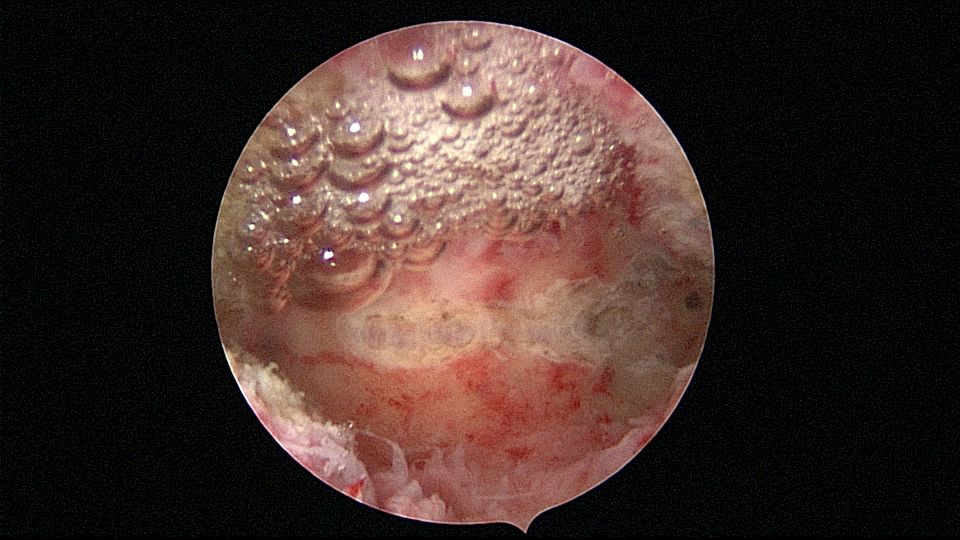

患者33岁,G5P2,顺产2次,胎停清宫后月经量减少,外院B超提示宫腔粘连。2021年5月宫腔镜探查,宫腔重度粘连,宫腔狭小,右侧输卵管开口可见,左侧输卵管开口未见,单极电针分粘,恢复宫腔形态,显露左侧输卵管开口(僵硬)。2021年6月宫腔镜二探取球囊,宫腔形态正常,双侧输卵管开口可见,宫内膜薄。2022年7月自然妊娠,2023年3月孕39+周顺产分娩。现38岁,G6P3,顺产3次。